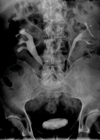

See also Part 2 and Part 3. Case 1 A 59-year-old man presented with right loin pain. His GP arranged for him to have an intravenous urogram (IVU) and subsequent CT urogram performed. What is the likely diagnosis? What are...